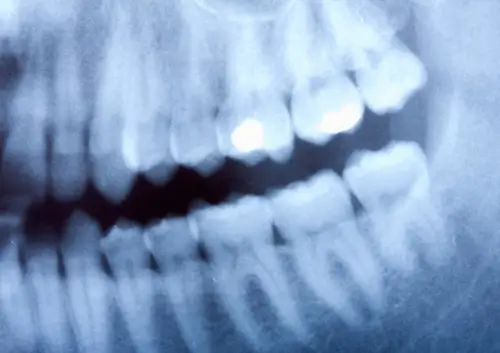

Dental imaging plays a crucial role in diagnosing and treating oral health conditions. If you’ve visited an oral surgeon recently, you may have noticed that traditional film X-rays have been replaced by digital alternatives. This technological advancement has revolutionized the field of oral surgery, offering numerous benefits for both patients and practitioners. Digital X-rays provide enhanced image quality, allowing oral surgeons to detect issues earlier and plan treatments with greater precision.

Digital X-rays have dramatically enhanced the diagnostic capabilities of modern oral surgery practices. The technology produces images with significantly higher resolution compared to traditional film X-rays, making it easier to detect even the smallest abnormalities in teeth, bones, and surrounding tissues. This improved clarity allows oral surgeons to identify potential issues such as hidden decay, bone loss, and infections in their earliest stages, often before symptoms become noticeable to patients.

Another significant advantage is the ability to manipulate digital images after they’ve been captured. Oral surgeons can zoom in on specific areas of concern, adjust contrast and brightness, and apply specialized filters to highlight particular structures. These enhancement features are invaluable when examining complex anatomical structures like the temporomandibular joint or when planning intricate surgical procedures such as implant placement. The detailed visualization provided by digital X-rays contributes to more accurate diagnoses and more precise treatment planning.